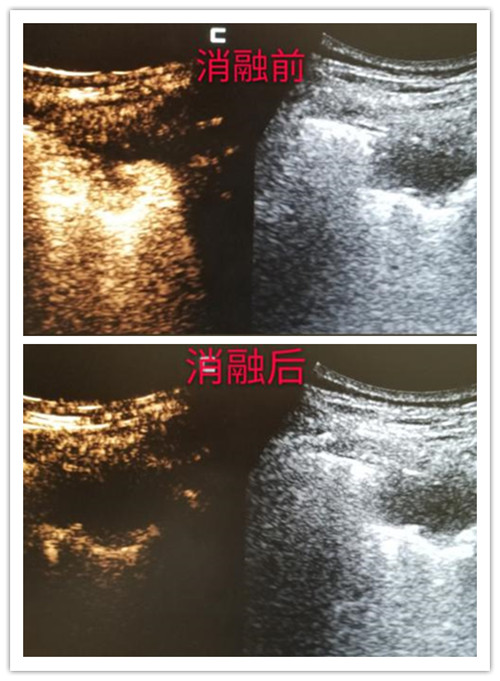

3、超声引导下微波消融术

微波消融术是治疗肿瘤微创治疗技术,它的原理使局部肿瘤组织凝固性坏死,最终形成液化灶或纤维化,起到原位灭活肿瘤组织的作用,对于直径≤3cm的肺部肿瘤,微波消融可以达到一次完全灭活肿瘤的效果,而对于较大的肿瘤,往往需要多针、多次治疗,微波消融联合手术、放疗、化疗可显著延长患者的生存期,改善患者的功能状态。微波消融具有疗效好、创伤小、痛苦小、恢复快、适用范围广等特点,现已广泛适用于临床。

超声引导下肺部肿瘤微波消融术